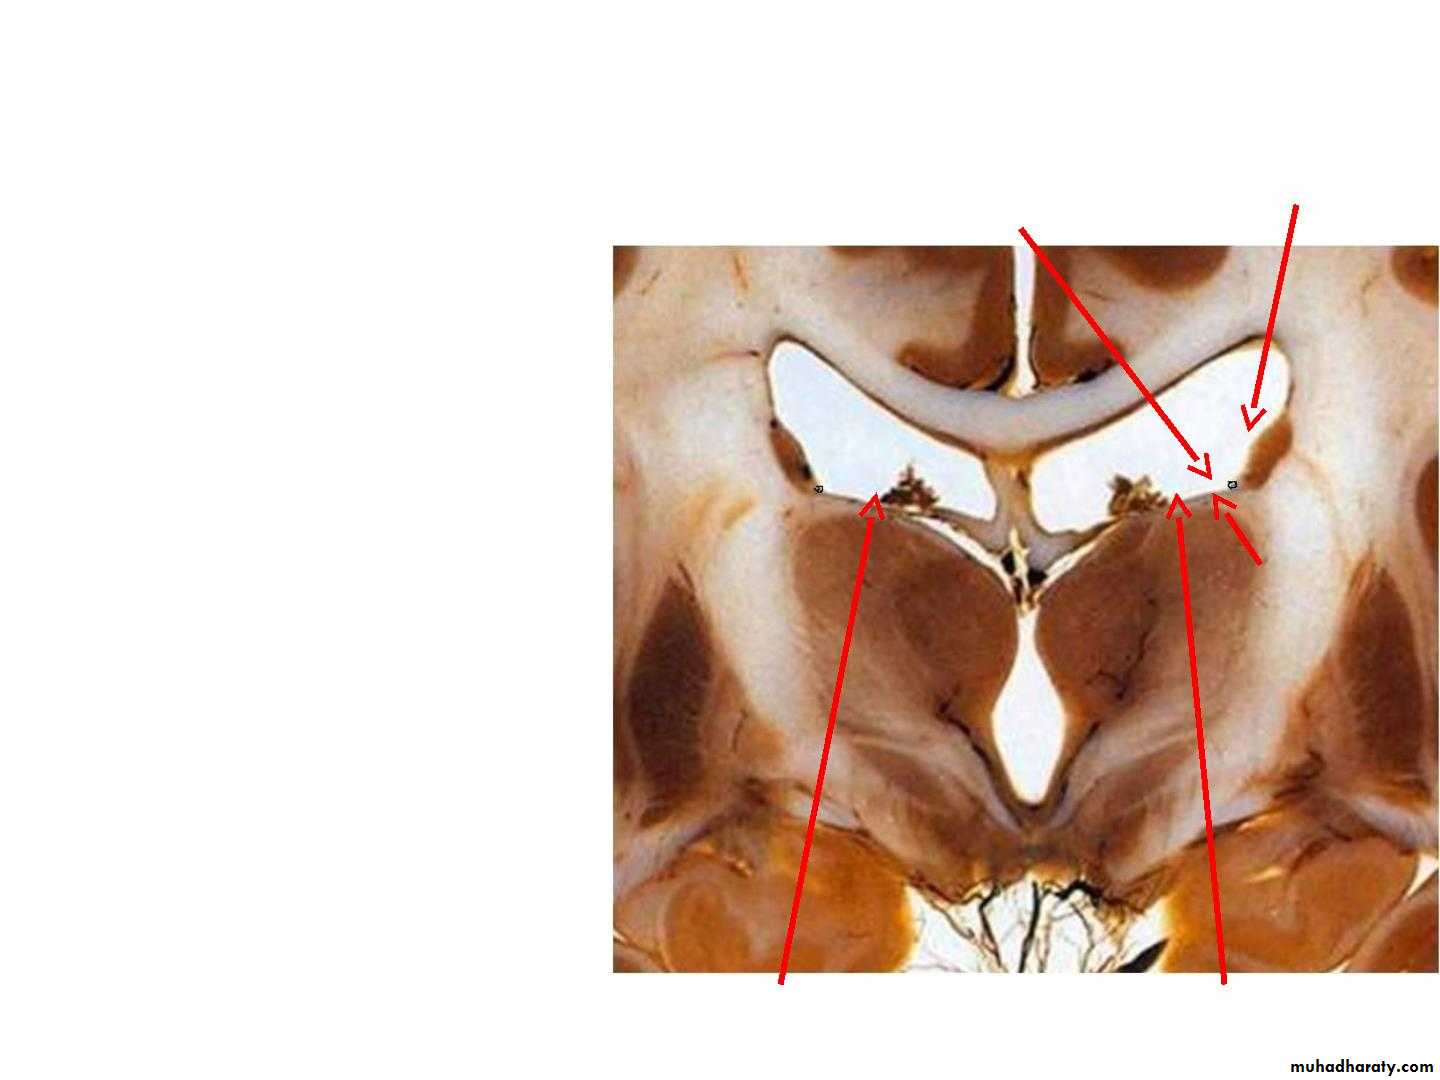

• Anatomy of the thalamus

• • Definition: The thalamus is a large,• paired, ovoid mass of nuclei located

• in the diencephalon, and form the

• upper 2/3 of the lateral wall of the

• third ventricle.

• • Relations :

• • Rostrally: the interventricular

• foramen.

• • Ventrally: the hypothalamic sulcus.

• • Posteriorly: the posterior

• commissure

• • Medially: the third ventricle

• • Laterally: the posterior limb of the

• internal capsule

• Relations

• Dorsal: lateral ventricle• Rostrally

• interventricular

• foramen

• Medial: 3rd

• ventricle

• Lateral :

• Internal

• capsule

• Ventral: Subthalamus & Hypothalamus

• Caudal: midbrain